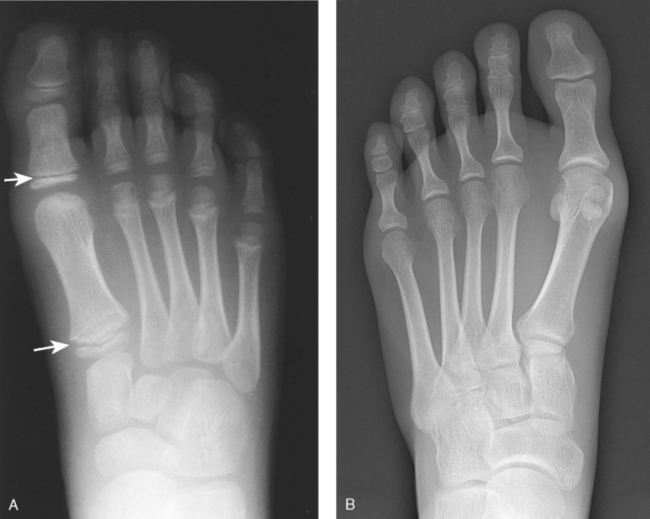

The five metatarsals are numbered one to five beginning at the medial or great toe side of the foot. The metatarsals consist of a body and two articular ends. The expanded proximal end is called the base, and the small, rounded distal end is termed the head. The five heads form the “ball” of the foot. The first metatarsal is the shortest and thickest. The second metatarsal is the longest. The base of the fifth metatarsal contains a prominent tuberosity, which is a common site of fractures.

Beneath the head of the first metatarsal are two small bones called sesamoid bones. They are detached from the foot and embedded within two tendons. These bones are seen on most adult foot radiographs. They are a common site of fractures and must be shown radiographically (see Fig. 6-2).

| Jones | Avulsion fracture of the base of the fifth metatarsal |

Structures shown: The resulting image shows an AP (dorsoplantar) projection of the tarsals anterior to the talus, metatarsals, and phalanges (Figs. 6-43 to 6-45). This projection is used for localizing foreign bodies, determining the location of fragments in fractures of the metatarsals and anterior tarsals, and performing general surveys of the bones of the foot.

Structures shown: The resulting image shows the interspaces between the following: the cuboid and the calcaneus, the cuboid and the fourth and fifth metatarsals, the cuboid and the lateral cuneiform, and the talus and the navicular bone. The cuboid is shown in profile. The sinus tarsi is also well shown (Fig. 6-47).